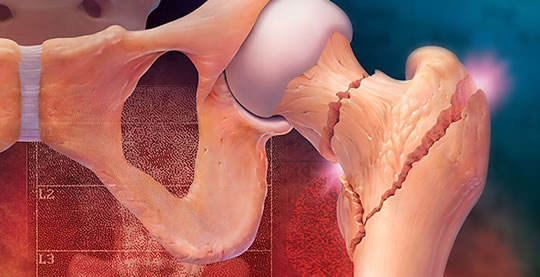

Tratamos no solamente lesiones traumáticas, deportivas, de accidentes laborales, de tránsito, etc. sino también todo tipo de enfermedades del aparato osteo-articular, incluyendo deformidades congénitas como luxaciones de cadera, deformidades de los pies, manos, rodillas; enfermedades de la columna como escoliosis congénita o adquirida, enfermedades degenerativas de las articulaciones como artrosis de cadera y de rodilla especialmente.

Para todos estos tratamientos utilizamos múltiples métodos tanto ortopédicos como quirúrgicos, llegando de esta manera al recambio articular en el caso de prótesis de rodilla, cadera, hombro, etc.